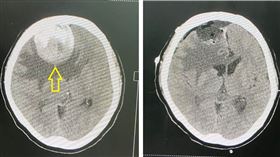

女作息正常長期頭暈 昏倒才知腦中埋炸彈

46歲的艾小姐,平時作息正常且無不良嗜好,長期感到頭...